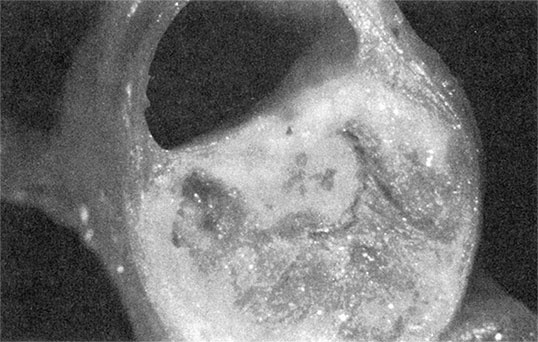

Иллюстрация к книге — Здоровое сердце. Издание XXI века [i_010.jpg]

Рисунок 1.7а. При разрыве бляшки ее содержимое попадает в кровь и вызывает образование тромба в сосуде. Снимок предоставлен доктором Майклом Дж. Дэвисом